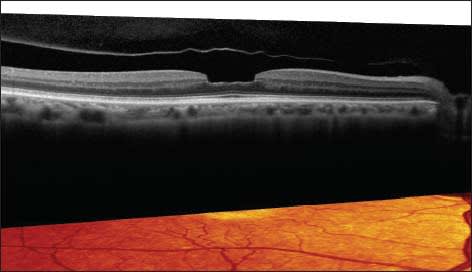

The patient may have an undiagnosed macular issue that is virtually impossible to see on ophthalmoscopy, he says, “but OCT will pick it up in a heartbeat.” (Figures 1-3) OCT can now provide anterior segment information that may be invaluable in gaining insight into why patients may not be happy with their outcomes from surgery.

Figure 1. Vitreomacular traction: One sees almost nothing unusual on exam but there is impressive pathology on OCT.